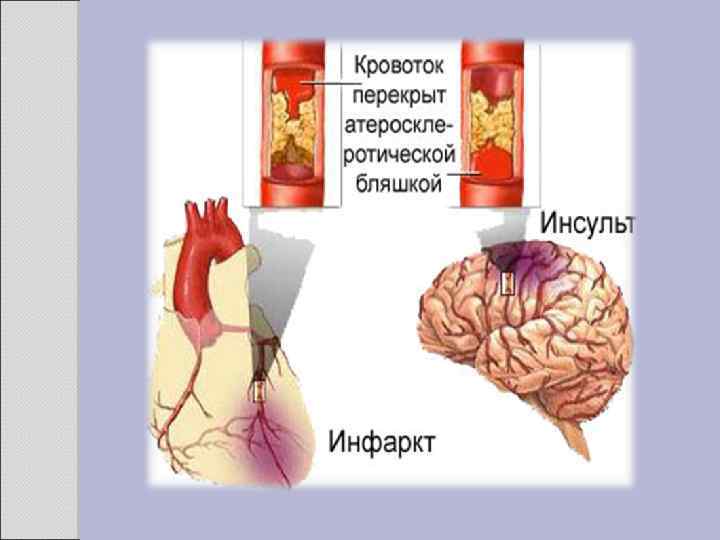

2. 1 АТЕРОСКЛЕРОЗ Атеросклероз — хроническое заболевание эластического и мышечно-эластического типа, возникающее вследствие нарушения липидного обмена и сопровождающееся отложением холестерина и некоторых фракций липопротеидов в интиме сосудов. Отложения формируются в виде атероматозных бляшек. Последующее разрастание в них соединительной ткани (склероз), и кальциноз стенки сосуда приводят к деформации и сужению просвета вплоть до облитерации (закупорки). Этиология На данный момент единой теории возникновения данного заболевания нет. Выдвигаются следующие варианты, а также их сочетания: • теория липопротеидной инфильтрации — первично накопление липопротеидов в сосудистой стенке, • теория дисфункции эндотелия — первично нарушение защитных свойств эндотелия и его медиаторов, • аутоиммунная — первично нарушение функции макрофагов и лейкоцитов, инфильтрация ими сосудистой стенки, • моноклональная — первично возникновение патологического клона гладкомышечных клеток, • вирусная — первично вирусное повреждение эндотелия (герпес, цитомегаловирус и др. ), • перекисная — первично нарушение антиоксидантной системы, • генетическая — первичен наследственный дефект сосудистой стенки, • хламидиозная — первичное поражение сосудистой стенки хламидиями, в основном, Chlamydiapneumoniae. • гормональная — возрастное повышение уровня гонадотропных и адренокортикотропных гормонов приводит к повышенному синтезу строительного материала для гормонов-холестерина.

Клиника Клинические проявления часто не соответствуют морфологии. При патологоанатомическом вскрытии обширное и выраженное атеросклеротическое поражение сосудов может оказаться находкой. И наоборот, клиника ишемии органа может появляться при умеренной облитерации просвета сосуда. Характерно преимущественное поражение определенных артериальных бассейнов. От этого зависит и клиническая картина заболевания. Поражение коронарных артерий постепенно приводит к коронарной недостаточности, проявляющейся ишемической болезнью сердца. Заинтересованность церебральных артерий вызывает либо преходящую ишемию мозга либо инсульты. Поражение артерий конечностей — причина перемежающейся хромоты и сухой гангрены. Атеросклероз брыжеечных артерий ведет к ишемии и инфаркту кишечника (мезентериальный тромбоз). Также возможно поражение почечных артерий с формированием почки Голдблатта. Даже в пределах отдельных артериальных бассейнов характерны очаговые поражения — с вовлечением типичных участков и сохранностью соседних. Так, в сосудах сердца окклюзия наиболее часто возникает в проксимальном отделе передней межжелудочковой ветви левой коронарной артерии. Другая типичная локализация — проксимальный отдел почечной артерии и бифуркация сонной артерии. Некоторые артерии, например внутренняя грудная, поражаются редко, несмотря на близость к коронарным артериям и по расположению, и по строению. Атеросклеретические бляшки часто возникают в бифуркации артерий — там, где кровоток неравномерен; иными словами, в расположении бляшек играет роль локальная гемодинамика (см. патогенез).

Диагностика заболеваний связанных с атеросклерозом включает: • опрос больного и выяснение симптомов болезни: симптомы ишемической болезни сердца, симптомы нарушения мозгового кровообращения, перемежающаяся хромота, симптомы брюшной жабы и пр. ; • общий осмотр больного: признаки старения организма, выслушивание систолического шума в очаге аорты; • обязательно пальпация всех артерий, доступных к пальпации: аорта, наружные подвздошные артерии, общие бедренные артерии, подколенные артерии, артерии тыла стопы и задней большеберцовой артерии, лучевой и локтевой артерий, сонных артерий; • определение систолического шума над аускультативными точками артерий; • при подозрении на поражение артериального русла нижних конечностей - определение капиллярного ответа; • определение концентрации холестерина в крови и определение липидного баланса крови; • рентгенологическое исследование органов грудной клетки, рентгенэндоваскулярные методы обследования; • ультразвуковое исследование сердца и органов брюшной полости и забрюшинного пространства; • доплерография сосудов конечностей, а лучше ультразвуковое дуплексное и триплексное сканирование артерий брахиоцефального отдела, артерий нижних конечностей, аортоподвздошного сегмента, а также транскраниальныйдоплер.